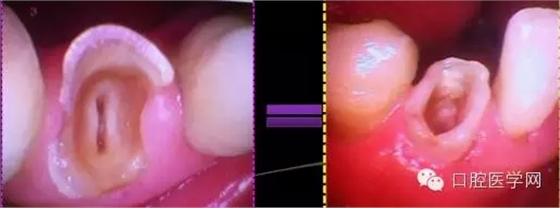

這個是到我這邊的牙合面照片

根管口沒有完全展開,我用8#Kfile疏通了下不是非常順暢,患者疼痛有可能是因為之前Kfile疏通的時候根尖有被激惹,或者是根管物有被退出根尖孔。